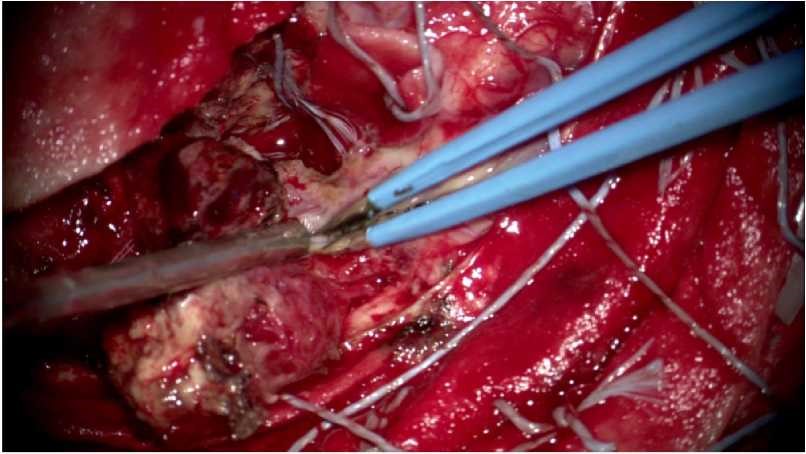

术中情况: